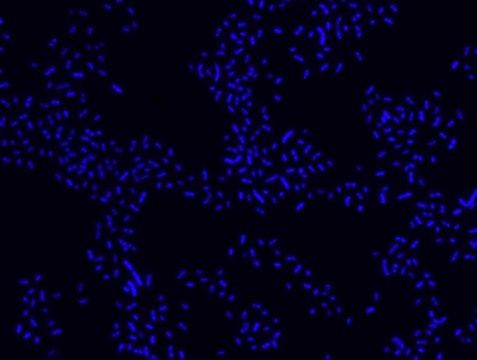

Proteus probe specifically recognizes Proteus species (see images of Proteus vulgaris and Proteus mirabilis). Moreover, it was shown that this probe recognizes Proteus penneri and Proteus hauseri.16

FISH technique was successfully used for clinical detection of Proteus spp. in artificial urine medium and urine samples from patients with UTIs. The probe was able to detect 11 strains of P.mirabilis, 6 strains of P. vulgaris, 2 strains of P.penneri and one strain of P. hauseri.16 The probe can also be used to detect P. mirabilis and P. vulgaris pure culture (as described in the figure legends). FISH can also be implicated to detect Proteus spp. in colon sections embedded in paraffin.17,18 Moreover, FISH can be implicated to identify Proteus spp. in the gut of the medicinal leech.19